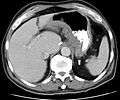

CT scan showing Crohn's disease in the fundus of the stomach

CT and MRI scans are useful for evaluating the small bowel with enteroclysis protocols.[115] They are also useful for looking for intra-abdominal complications of Crohn's disease, such as abscesses, small bowel obstructions, or fistulae.[116] Magnetic resonance imaging (MRI) is another option for imaging the small bowel as well as looking for complications, though it is more expensive and less readily available.[117]